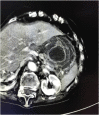

Introduction: The gastric volvulus is a rare condition in which the stomach, or part of it, rotates on its axis, for over 180°, constituting a surgical emergency. Even more rare is gastro-gastric intussusception. A delay in their diagnosis and treatment can have fatal consequences PRESENTATION OF CASE: An 82-year-old woman was admitted to the Surgery Unit with a two-day history of abdominal pain associated at first with coffee vomiting and, subsequently, with unproductive retching and oligoanuria. Physical examination showed severe dehydration, fever, at the abdominal level, palpation caused a marked tenderness of all quadrants, with signs of peritonism. Laboratory test showed showed neutrophilic hyperleukocytosis and high C reactive protein level. Abdominal computed tomography revealed an acute intrathoracic gastric volvulus and a gastrogastric intussuception. The patient was submitted to exploratory laparotomy, subtotal gastrectomy with Roux en Y anastomosis and simple plastic of the esophageal hiatus. At the end of the surgery, however, the patient died of your septic shock.

Discussion: The traditional treatment for a patient with acute gastric volvulus is an immediate surgical intervention to derotate the stomach and prevent vascular insufficiency. In the presence of necrosis or gastric perforation, resection should be performed. The few cases of gastrogastric intussusception described in the literature have been treated with sub-total gastrectomy and gastro-jejunal anastomosis. Any delay in diagnosis and treatment can prove fatal.